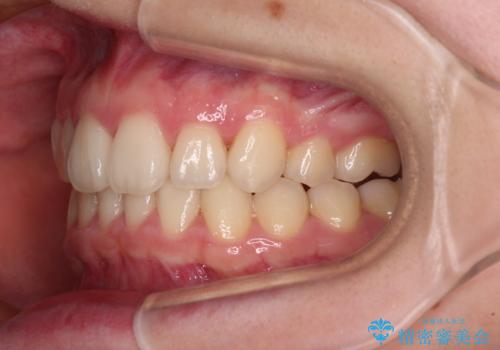

上顎のみの抜歯矯正 前歯のデコボコを改善する

奥歯の咬み合わせがなかなか定まらず、スペースが閉じるまでに時間がかかりましたが、最終的には正中を合わせることもできました。